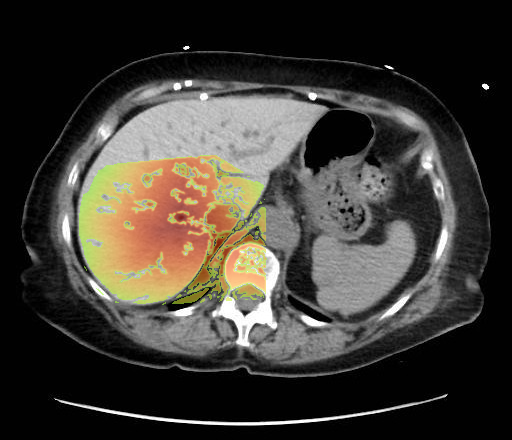

- Non-contrast axial CT through the upper abdomen.

- The liver (image-left, patient-right) demonstrates diffusely increased parenchymal attenuation relative to spleen (image-right, patient-left).

- Liver contour appears smooth, no focal mass identified at this level.

- Spleen (image-right, patient-left) of normal size and attenuation.

Diffuse hepatic parenchymal hyperattenuation due to amiodarone deposition (amiodarone liver). The liver is abnormally hyperdense on a non-contrast CT compared to the spleen, which is a classic imaging feature of amiodarone-induced hepatic iodine deposition. The attenuation difference eliminates common diffuse hypodensity causes such as steatosis, iron overload, or Wilson’s disease. Context consistency: Consistent. The uploader’s diagnosis of "Amiodarone Liver" directly matches the imaging appearance. Confidence: 90%.